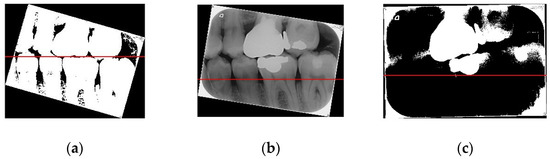

Figure 8 shows the importance of image preprocessing through the Gaussian filter and Otsu’s thresholding for image cropping.

Figure 8.

(a) Image processed through the Gaussian filter and Otsu’s thresholding, where the red line separates the upper and lower teeth; (b) image without any processing, where the red line separating the upper and lower teeth is very imprecise; (c) image processed only through Otsu’s thresholding, where the red line separating the upper and lower teeth is also imprecise.